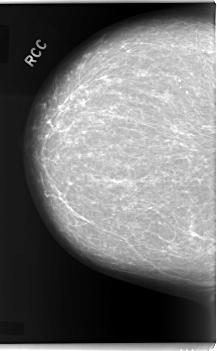

Digital Database for Screening Mammography

Volume: cancer_09 Case: C-0084-1

C_0084_1.RIGHT_CC

RIGHT_CC LINES 5960 PIXELS_PER_LINE 3688 BITS_PER_PIXEL 12 RESOLUTION 50 NON_OVERLAY